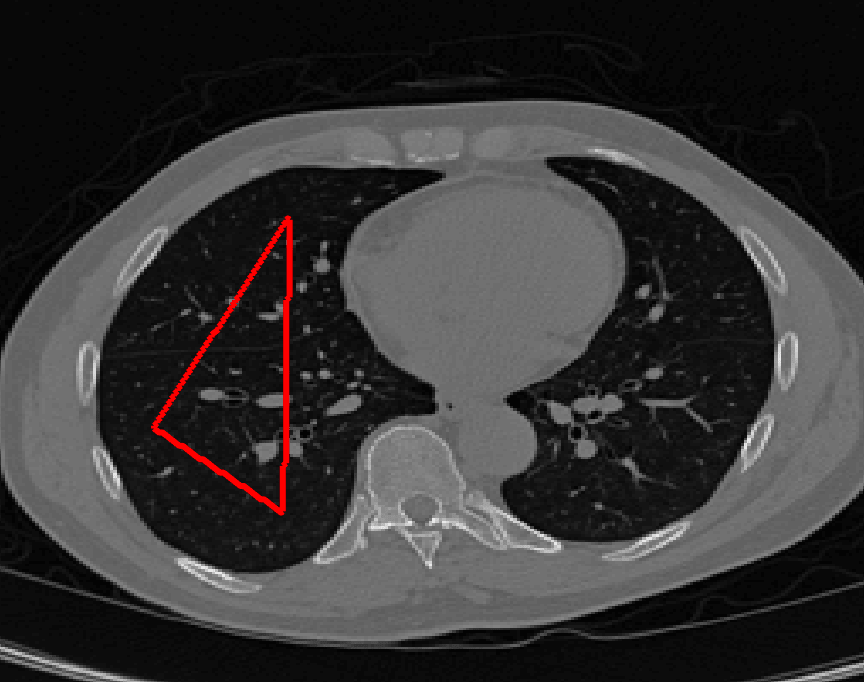

The motivation for this work comes from observing contradictions in using piecewise-constant intensity fitting terms in selective segmentation. Whilst good results are possible with this approach, the exceptional cases lead to severe limitations in practice. This is quite common in medical imaging as demonstrated in Fig. 1, where the target foreground has a low intensity. Given that the corresponding background includes large regions of low intensity, the optimal average intensities for this segmentation problem are and . For cases where , we see that by (1), almost everywhere in the domain . This means that it is very difficult to achieve an adequate result, without an over-reliance on the user input or parameter selection.

The central premise for applying Chan-Vese type methods is the assumption that the image approximately consists of

where is noise, is the characteristic function of the region , for respectively. The idea of selective segmentation is to incorporate user input to apply constraints that exclude regions classified as foreground, based on their location in the image. We use a distance constraint which penalises the distance from the user input markers. However, a key problem for selective segmentation is that for cases where the optimal intensity values and are similar, the intensity fitting term will become obsolete as the contour evolves. This is illustrated in Fig. 3. The purpose of our approach is to construct a model that is based on assumptions that are consistent with the observed image and any homogeneous target region of interest. A common approach in selective segmentation is to discriminate between objects of a similar intensity Rada:13 ; Geo ; CDSS . However, the fitting terms in previous formulations Klodt:13 ; Rada:13 ; Geo ; CDSS aren’t applicable in many cases as there are contradictions in the formulation in this context. We will address this in detail in the following section.